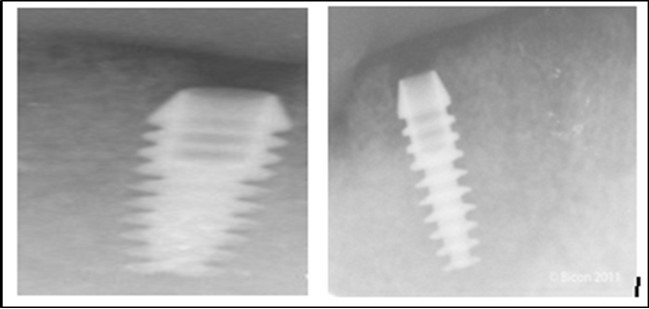

Figure 5.a,b. Post-insertion radiographics in the mandibular area right,left,

Figure 6.Panoramic radiograph after the insertion of two implants